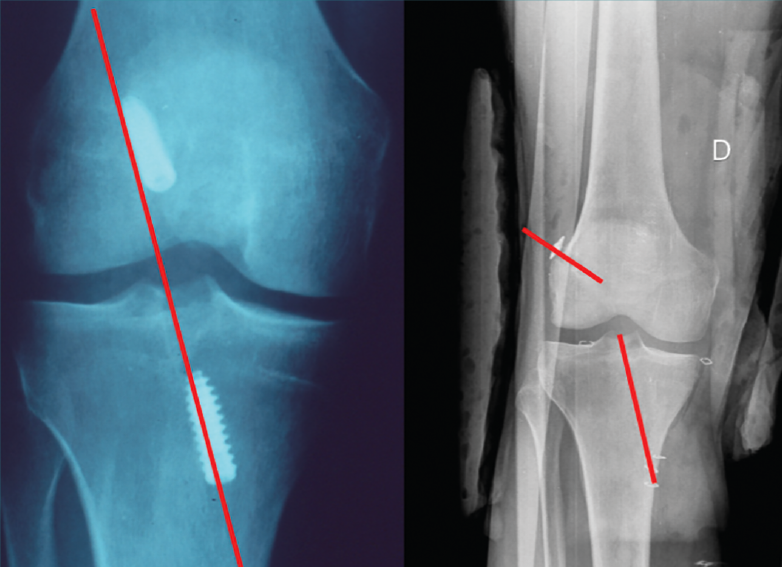

Figura 1. Imagen radiológica que permite identificar una técnica de reconstrucción transtibial o “monotúnel” (izquierda) respecto a una técnica anatómica (derecha).

El estudio radiológico recomendado debería incluir proyecciones anteroposteriores y laterales, axiales de rótula, telemétricas de la extremidad inferior y también en posición de Schuss (en carga y con unos 30° de flexión de la rodilla). La radiología simple va a permitir identificar qué técnica quirúrgica se realizó inicialmente y qué material se utilizó para la fijación (Figura 1). La proyección en Schuss permite observar si existen cambios degenerativos en los compartimentos femorotibial interno o externo de la rodilla de forma más precisa que con la radiología simple en decúbito supino. Finalmente, la radiografía telemétrica de las extremidades inferiores va a permitir conocer el eje mecánico de la extremidad. La existencia de deformidades en el plano coronal se ha asociado a un incremento de la solicitación mecánica del LCA y también del riesgo de rotura de la plastia (Figura 2)(21).